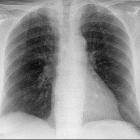

Schrittmacherkabel bei epikardialen Schrittmacher. Zusätzlich Trikuspidalklappenersatz bei Ebstein-Anomalie.